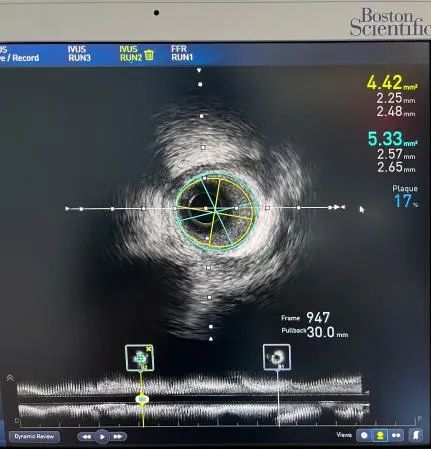

术中,经右桡动脉入路穿刺后,行冠脉造影提示:冠脉分布为右冠优势型,左主干未见明显狭窄,前降支近端狭窄60%,中段可见心肌桥,收缩期狭窄70%,舒张期恢复正常,对角支近端狭窄50%, 左回旋支未见狭窄,第一钝缘支细小,未见狭窄,右冠、左室后支及后降支未见狭窄。随后葛均波院士团队拟行IVUS+FFR联合评估,以期为患者制定最合适的治疗策略。首先,取6F EBU 3.5指引导管将Runthrough NS导丝送至前降支远端。随后,使用Polaris血管内超声系统的FFR测量功能,于前降支送入COMET™Ⅱ压力导丝,给予ATP达最大充血状态后,行FFR检查,提示FFR为0.85。为进一步分析患者血管内斑块情况,经6F EBU 3.5指引导管将Runthrough NS导丝分别送至前降支及对角支,使用Polaris血管内超声系统的IVUS检测功能,于前降支及对角支分别送入Opticross超声成像导管40 Mhz回撤行IVUS检查,可见前降支中段心肌桥,近端可见少许脂质斑块伴管腔负性重构,对角支可见近端少许斑块伴管腔负性重构。

前降支IVUS截图

患者前降支IVUS结果